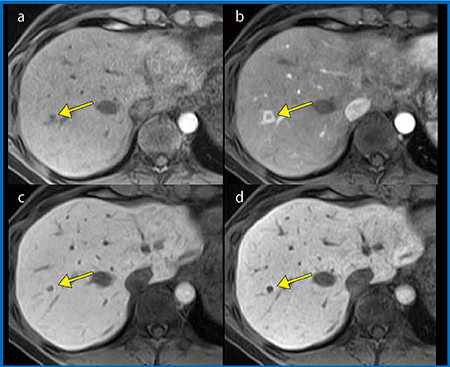

TRILLIUM OVALを用いたEOB造影MRI撮像では,図2のように,動脈相(b)で肝腫瘍の明瞭なリング状濃染が描出されており,転移性肝腫瘍と診断することができた。

当院のEOB造影MRIは,TIGRE(T1-weighted GRadient Echo sequence)シーケンスに脂肪抑制“H-Sinc”を併用して撮像している(図3)。TIGREは,k空間の中心から辺縁に向かって放射状に充填され,各セグメントは撮像時間中,常に中心から辺縁に向かって繰り返される。そのためコントラストは撮像時間の平均となり,動脈相のタイミングを外すことなく撮像できる。そこでわれわれは,ダイナミックCTと比較して,HCCの多血性病変に対するTIGREの有用性の検討を行った4)。

結果として,EOB造影MRIの動脈相は,ダイナミックCTと比較し,HCCの多血性をより正確に評価できていることが判明した。よって,TIGREシーケンスを用いた場合,EOB造影MRIは,ダイナミックCTよりもHCCの血流をより正確に評価でき,HCC診断への有用性が期待される。

図2 EOB造影MRI 転移性肝腫瘍

a:pre b:arterial phase

c:hepatobiliary phase

d:hepatobiliary phase(thin slice)